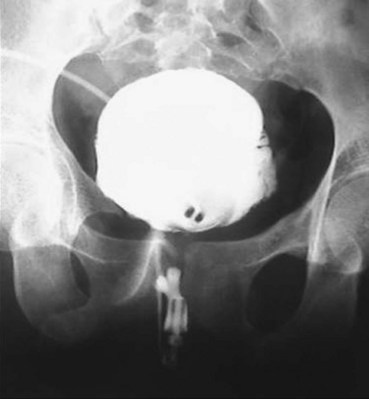

A dense, flame-shaped collection of contrast material in the pelvis is characteristic of extraperitoneal extravasation (Fig. 88–9). Depending on fascial integrity, contrast material may extend beyond the confines of the pelvis and be visualized in the retroperitoneum, scrotum, phallus, thigh, and/or abdominal wall. The amount of extravasation is not always proportional to the extent of bladder injury. Intraperitoneal extravasation is identified when contrast material outlines loops of bowel and/or the lower lateral portion of the peritoneal cavity.

Figure 88–9 Plain film cystogram reveals extraperitoneal bladder rupture with extravasation into scrotum. Surgical exploration revealed anterior bladder neck and prostatic urethral laceration.